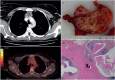

The diagnosis of a mediastinal mass may be challenging for clinicians, since lesions arising within the mediastinum include a variety of disease entities, frequently requiring a multidisciplinary approach. Age and sex represent important information, which need to be integrated with imaging and laboratory findings. In addition, the location of the mediastinal lesion is fundamental; indeed, we propose to illustrate mediastinal diseases based on the compartment of origin. We consider that this structured approach may serve as hint to the diagnostic modalities and management of mediastinal diseases. In this review, we present primary mediastinal tumours in the evolving context of new diagnostic and therapeutic tools, with recently described entities, based on our own experience with >900 cases encountered in the past 10 years.